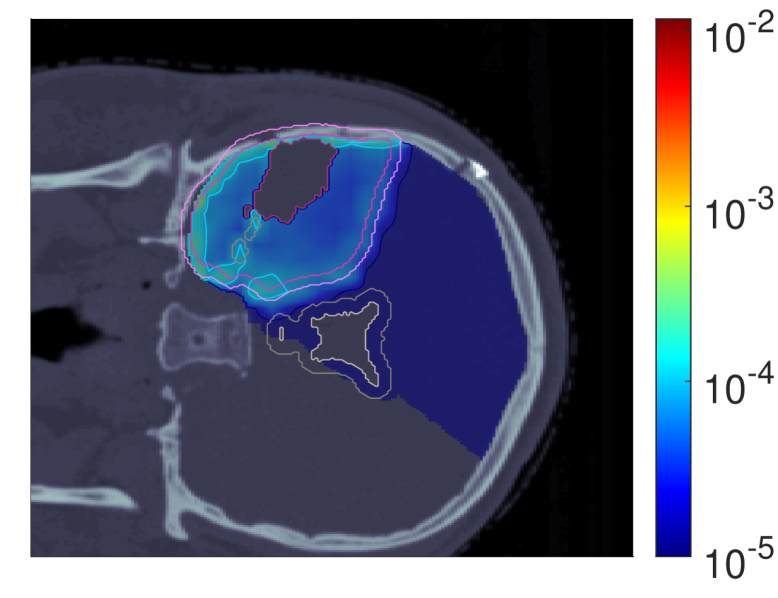

III.A.3 Probability of lesion origin pp

Figure 7 shows the POLO maps resulting from voxel-wise evaluation of the sigmoid-transformed linear predictor η\eta from Equation 1 with the input slice images for dRBE,fxd_{RBE,fx} and ldl_{d}.

NTCP30 %NTCP\approx{$30\text{\,}\mathrm{\char 37\relax}$} NTCP20 %NTCP\approx{$20\text{\,}\mathrm{\char 37\relax}$} NTCP10 %NTCP\approx{$10\text{\,}\mathrm{\char 37\relax}$}

pp (NTCPp)(NTCP_{p})

Refer to caption Refer to caption Refer to caption

pp (LSEp~)(LSE_{\tilde{p}})

pp (H~p)(\tilde{H}_{p})

pp (H~p~)(\tilde{H}_{\tilde{p}})

Figure 7: Optimal slice images of the probability of lesion origin pp for NTCPpNTCP_{p}, LSEp~LSE_{\tilde{p}}, H~p\tilde{H}_{p} and H~p~\tilde{H}_{\tilde{p}} at different NTCP levels. Considering the slice images for dRBE,fxd_{RBE,fx} and ldl_{d} from Figure 3 and Figure 5, the calculated pp values can be deduced from the prediction model. For example, hot spots are primarily found where high dRBE,fxd_{RBE,fx} values meet high ldl_{d} values, and for the voxels inside the 4 mm4\text{\,}\mathrm{mm} ventricular fringe where bb boosts the probability prediction. We take from these results that the POLO model-based optimization of the LGG sample patient’s proton plan achieves its goal, i.e., reducing pp in the region of interest.

For NTCPpNTCP_{p} and H~p\tilde{H}_{p}, we observed a (slight) reduction of dRBE,fxd_{RBE,fx} in the target volume and in the lower region overlapping with the VS, as well as a redistribution of ldl_{d} from the target volume to the margin of the PTV. Correspondingly, we see an overall reduction of pp in the target volume, together with an increasing attenuation of the hot spots around the marginal region of the PTV, and an elimination at the lower end of the VS. At strong down-regulation of the NTCP, the values are approximately one order of magnitude smaller, with peaks in the intersections to the 4 mm4\text{\,}\mathrm{mm} ventricular fringe and in regions where dRBE,fxd_{RBE,fx} and ldl_{d} intensify.

LSEp~LSE_{\tilde{p}} showed a decay of dRBE,fxd_{RBE,fx} inside but not outside the target volume, and almost constant values of ldl_{d}, and we recognize this pattern again in the pp distributions: hot spots are softened by the isolation of high-dose and high-LET regions, and the pp values in the target volume follow the negative trend for dRBE,fxd_{RBE,fx} at lower NTCP levels. Even the “dose gap” that occurs at an NTCP of 20 %20\text{\,}\mathrm{\char 37\relax} in the upper part of the target volume can be read from pp. Last, for H~p~\tilde{H}_{\tilde{p}} we can correlate the results for dRBE,fxd_{RBE,fx} and ldl_{d} again to understand pp. The higher ldl_{d} along the PTV margin is reflected by larger pp values and local hot spots, while the region around the GTV exhibits smaller pp values due to the reduction of dRBE,fxd_{RBE,fx}. At the lowest NTCP level, dRBE,fxd_{RBE,fx} contracts around the GTV, leaving only a slightly upward region at the left margin of the PTV which resembles the high-LET region, and hot spots where dRBE,fxd_{RBE,fx}, ldl_{d} and bb interact reinforcingly.

Globally, we observe an analogous shift in the “mass” of the pp distribution to lower values from the histograms in Figure 8. This indicates that the overarching goal of reducing pp during optimization can be fulfilled.